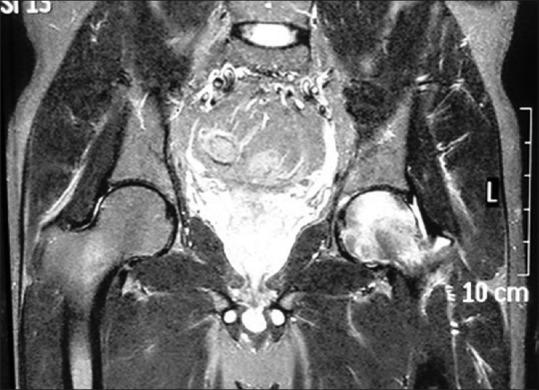

All the patients were treated conservatively by nonweight bearing mobilization, anti-inflammatory drugs, bisphosphonates, calcium, and Vitamin D supplements. None of our patients had any symptoms after 6 months of conservative management. The disease did not progress, and there was no evidence of hip joint involvement in any of the cases. Plain radiographs were not diagnostic in the early detection of TOH. Magnetic resonance imaging was found to be highly specific and sensitive in diagnosing TOH. The clinical condition of TOH is characterized by its acute onset of hip pain in middle-aged people, and its symptoms are out of proportion to the radiological findings.

所有患者均通过非负重活动、抗炎药物、双膦酸盐、钙剂和维生素D补充剂进行保守治疗。保守治疗6个月后,所有患者均无任何症状。疾病未进展,所有病例均无髋关节受累的证据。X线平片在TOH早期检测中无诊断价值。磁共振成像在诊断TOH方面具有高度特异性和敏感性。TOH的临床特征为中年患者急性髋部疼痛,其症状与影像学表现不成比例。